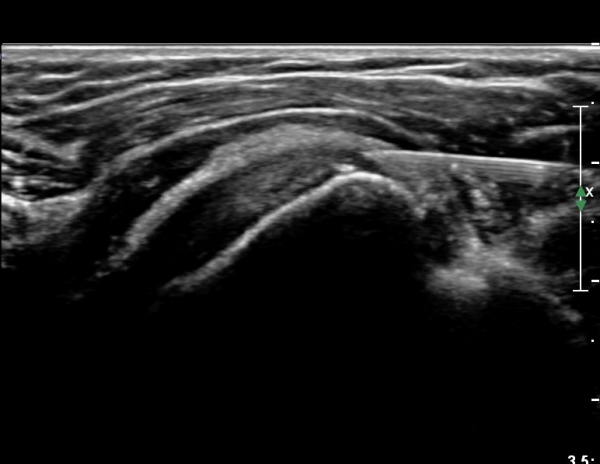

°ß°©ÇÏ±Ù°Ç ÇϺΠÁ¾´Ü¸é°Ë»ç¿¡¼­ °ß°©Çϱٰdz»  ÀÛÀº ¼®È¸È­ µ¢¾î¸®°¡ °üÂûµÈ´Ù(»çÁø 3, 4).

°ß°©ÇϱٰǠȾ´Ü¸é°Ë»ç¿¡¼­ ÇϺΠ°ß°©Çϱٰdz»  ÀÛÀº ¼®È¸È­ µ¢¾î¸®°¡ °üÂûµÈ´Ù(»çÁø 5).